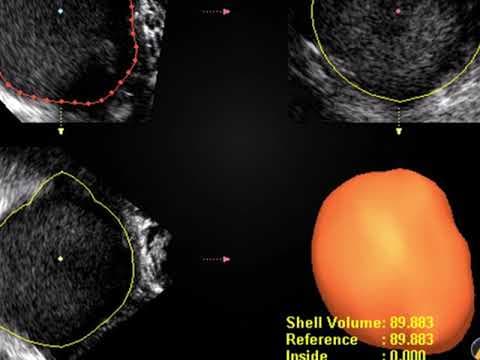

Premda su kardinalna obilježja ovog sindroma hiperandrogenizam i policističan izgled jajnika, niti jedan od pojedinačnih kriterija nije dovoljan da bi se postavila dijagnoza sindroma policističnih jajnika. Osnovna metoda u dijagnostici PCOS je ultrazvučni pregled. Koristi se transvaginalni ultrazvuk, prilikom čega se procjenjuje jesu li povećani jajnici, je li stroma - unutarnji dio jajnika koji proizvodi hormone, zadebljana, postoje li veliki broj folikula koji često tvore sliku ogrlice od perli ako su smješteni periferno ili stvaraju dojam mikrocističnosti kod difuznog rasporeda.

Dijagnoza PCOS prema Rotterdamskim kriterijima postavlja se kada žena ima najmanje dvije od sljedeće tri manifestacije: neredoviti menstrualni ciklusi ili anovulacija, povišena razina muških spolnih hormona i/ili jajnici čiji je volumen veći od 10 ml s najmanje 12 folikula na jednoj zamrznutom ultrazvučnoj slici jajnika. Nužno je isključiti ostala stanja sa sličnim znacima kao što su tumori koji stvaraju muške spolne hormone ili Cushingova bolest. Jajnici koji imaju policističan izgleda, s normalnom funkcijom i bez povišene razine muških spolnih hormona ne spadaju u sindrom policističnih jajnika i ne treba ih kao takve liječiti.